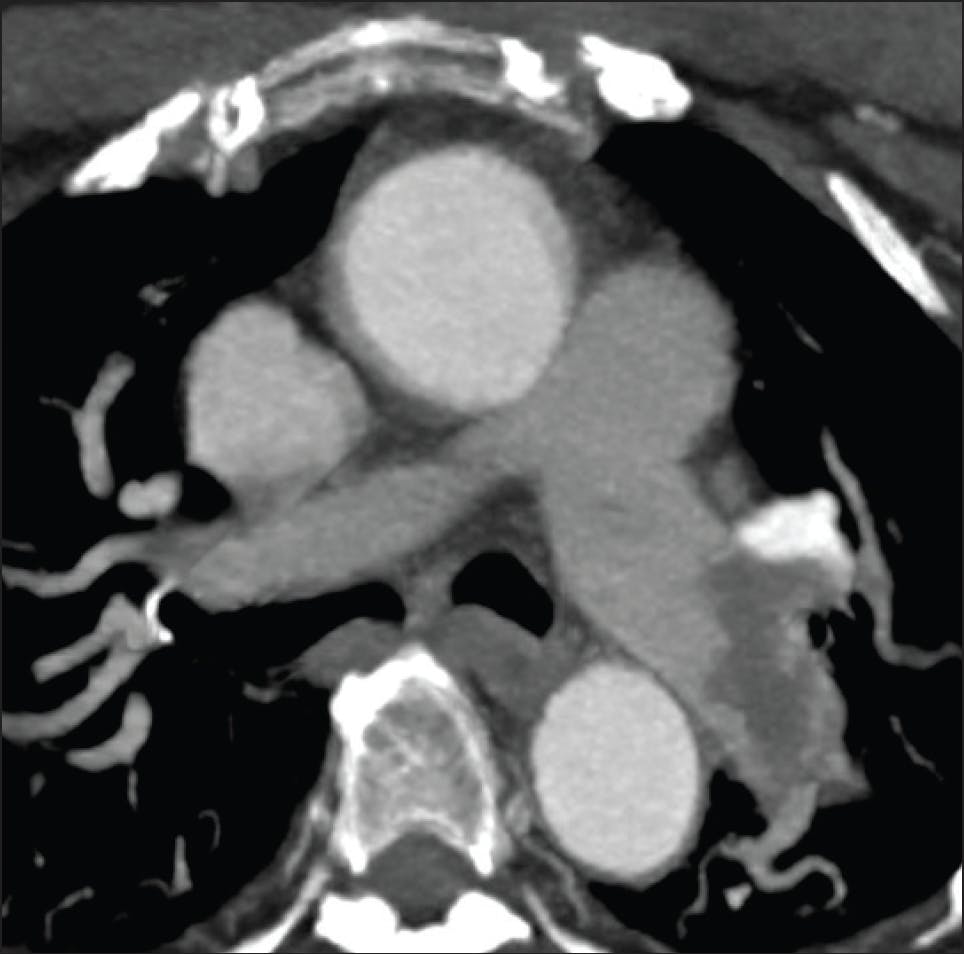

A female patient in her late 60s presented to the emergency department after experiencing a syncopal episode in her car. She reported mild shortness of breath but denied chest pain. Her medical history was notable for a prior postoperative blood clot, for which she was treated with warfarin. Initial vital signs showed a blood pressure of 142/92 mm Hg, a heart rate of 107 bpm, and an oxygen saturation of 95% on room air. Imaging demonstrated right heart strain with an RV/LV ratio of 1.6 and a saddle PE with moderate to large clot burden in the central PAs (Figure 1 and Figure 2). Using a pulmonary wedge pressure catheter, initial PA pressures (PAPs) were 71/26 mm Hg (mean, 45 mm Hg).

Figure 1. Preprocedural CT scan.